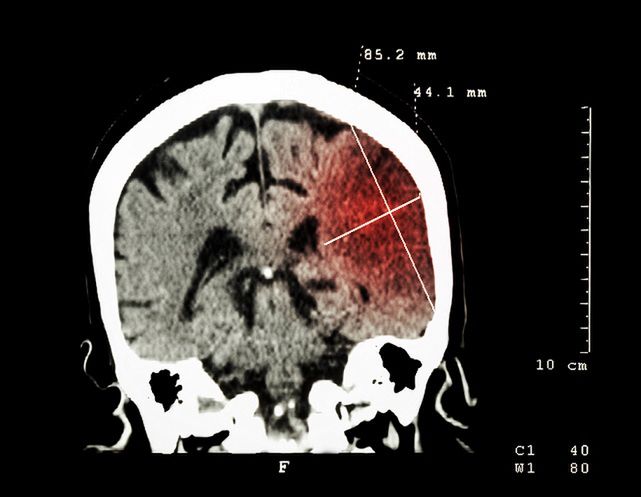

Krwiak podtwardówkowy (podoponowy) najczęściej jest skutkiem silnego urazu głowy, gdy doszło do złamania kości czaszkowych. Wszystkie krwiaki, a więc także krwiak podtwardówkowy, jest skutkiem powikłań po wszelkich urazach mózgu. Krwiaki uznaje się za najcięższe komplikacje pourazowe. Mogą one wystąpić nawet jako powikłania po upadku.

Krwiak podtwardówkowy charakteryzuje się zbieraniem krwi żylnej między oponami. Mowa tu o oponie twardej i pajęczej. Krwiak podtwardówkowy jest bardzo niebezpieczny, bowiem owe gromadzenie się krwi może doprowadzić nawet do pęknięcia żył w mózgu.

Krwiak podtwardówkowy powstaje w wyniku urazu głowy.